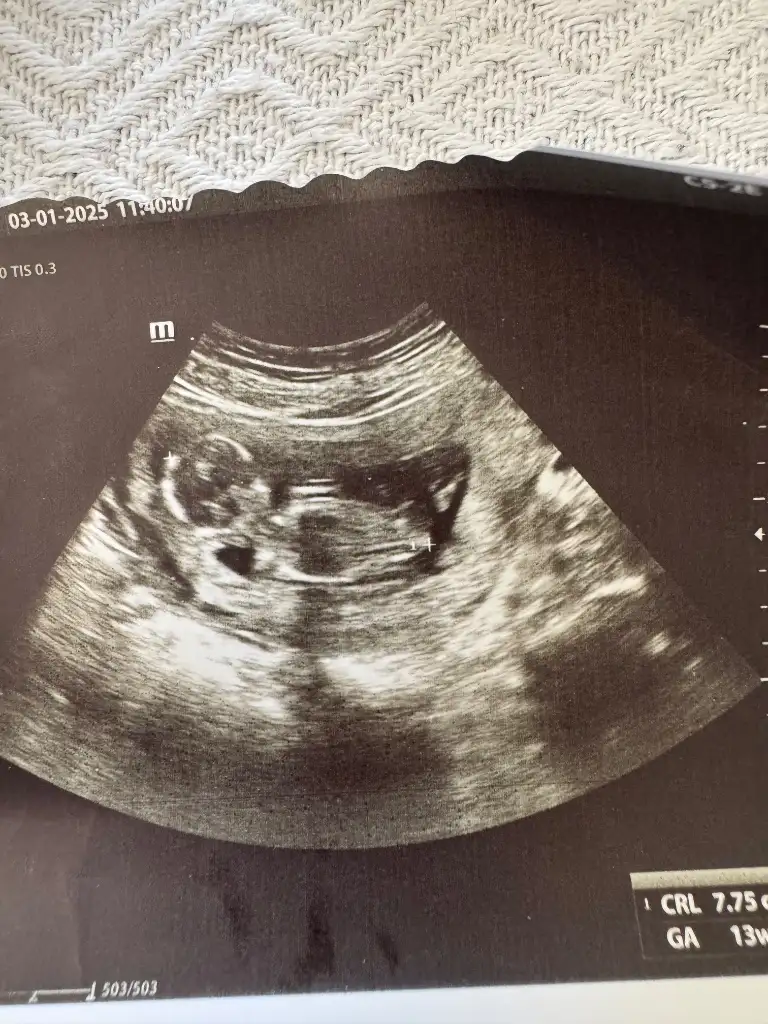

Kızlar 13. Haftamdayım dün gece sağ kasığımdan bacağıma vuran bir sızı ile asla doğru düzgün uyuyamadım ya sanki romatizmam varmış gibi sızladı durdu var mı yaşayan bunu

Pazartesi gece yaşadım öyle bir sızıydı ki uykudan uyandırdı.Dayanamadımm hemen doktora gittim sorun mu var acaba diye . Kızdılar hatta bana bu gayet normal işte bağlardan dokulardan falan görmeden rahat edemem dedim. Ultrasona aldı drek ağrı yerine koymasını istedim baktık ki bebiş orda tam ağrı olan yerde kese ve bebiş bu haftada hızlı büyüme yaşadığında ordaki bağların ağrısıymış rahat olsun yani içinbu arada bende 13+1 de gittim sağ taraftaydı benimde ağrım